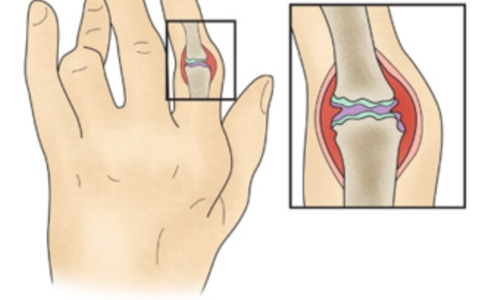

류마티스 관절염은 관절을 감싸는 활막에 만성 염증이 생겨 두꺼워지고, 관절 연골과 뼈가 손상되며 기능이 파괴되고 모양이 변형되는 질환입니다. 관절 증상뿐 아니라 빈혈, 미열, 전신 권태감과 함께 심장, 골다공증, 혈관염 등 다른 장기에도 영향을 줄 수 있습니다.

류마티스 관절염은 면역 체계의 이상으로 발생하는 질환입니다. 면역은 보통 외부 세균이나 바이러스 등을 방어하는 역할을 하지만, 류마티스 관절염에서는 면역이 자신의 세포와 조직을 공격하면서 관절에 염증을 일으킵니다. 이로 인해 원래 관절액을 만들어 관절 기능을 돕는 활막에 염증이 생기고, 염증이 오래 지속되면 관절이 점차 손상됩니다.

평소보다 몸이 붓는 부종을 경험한 적이 있으신가요? 류마티스 관절염이 생기면 과도한 염증으로 몸이 붓는 경우가 많아, 갑자기 잘 맞던 신발이 작게 느껴지거나 손마디가 부어오르면 초기 신호일 수 있습니다. 관절이 붓는 이유는 활막이 부풀고 주변에 관절 삼출액이 차기 때문이며, 이런 증상이 수개월에서 수년간 지속되면 관절 연골과 주변 조직이 손상되어 손가락이 휘거나 굳어 움직임이 어려워질 수 있습니다.

류마티스 관절염에서 흔히 나타나는 증상입니다. 관절을 둘러싼 활액막에 염증이 생기고, 병이 진행되면서 주변 연골과 뼈로 염증이 번지게 됩니다. 그 결과 온몸의 관절이 쑤시고 저리며 뻣뻣해지며, 관절 통증과 함께 열감, 압통, 부기 등이 동반됩니다. 이러한 증상은 주로 양쪽 관절에 나타나며, 손목, 팔꿈치, 무릎, 손가락, 발가락 등에서 많이 발생합니다.